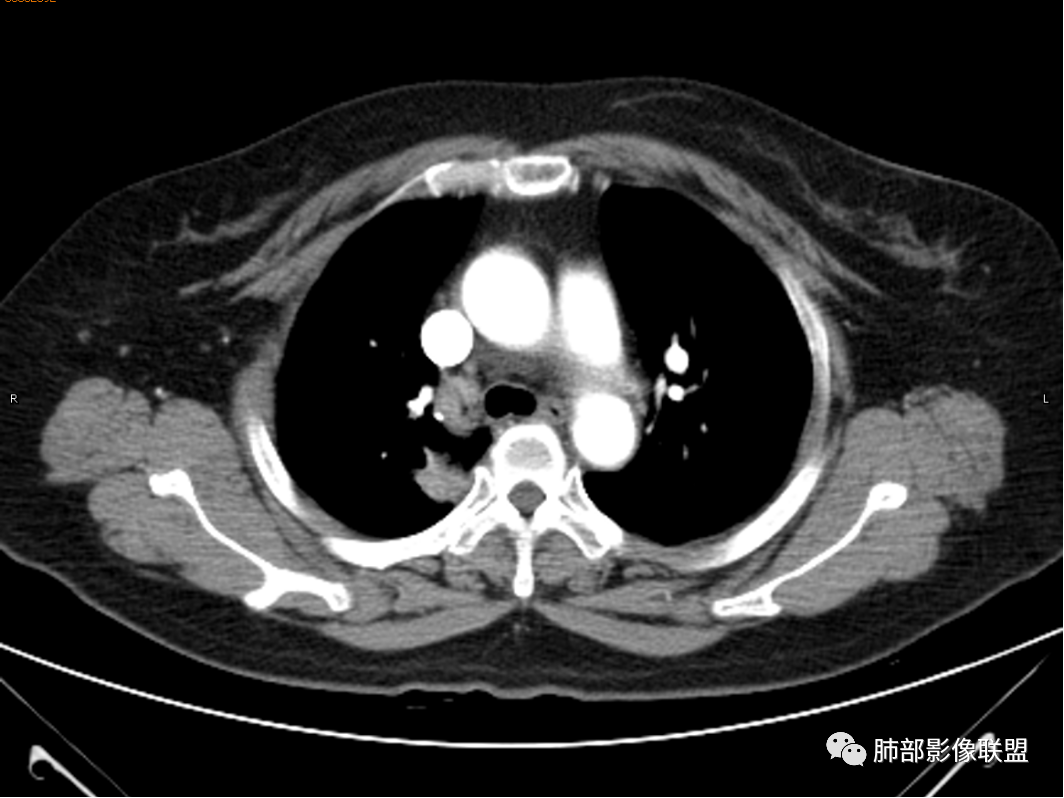

◆ 影像资料:

杨丽:老年女性,无肺气肿背景。右肺上叶后段胸膜下肿块,局部浅分叶,边缘见长软毛刺,支气管通入,临近叶间胸膜略增厚,增强扫描可见明显坏死,坏死边界清晰,壁较薄,其余病灶中等强化。纵隔小淋巴结。考虑:感染性病变,结核?鉴别囊肿伴感染。

玫:咳嗽,咳痰,痰中带血一个月,肿瘤标志物不高,右肺上叶肿块影,边界清晰,浅分叶及少许毛刺,增强扫描病灶边缘呈环形强化,病灶内见坏死区,考虑结核可能,鉴别腺癌。

蕊:环形强化,中心性坏死,坏死界线较清楚,肺门淋巴结肿大,考虑结核可能。

王秀仙:右肺上叶后段结节,分叶,部分边缘平直部分膨隆,周围可见磨玻璃晕,密度不均,中心低密度坏死,增强薄环状强化,坏死界线较清楚,纵膈小淋巴结肿大,考虑肉芽肿性病变,结核。鉴别鳞癌。

傅昌瑜:女性,咳嗽咳痰痰中带血1月。血常规、肿瘤标记物正常。CT:右上叶后段类圆形结节,内侧紧贴纵隔,前与右主支气管后壁分界不清。外后部分边缘平直收缩、矢状位可见U型凹陷、桃尖征,周围见边缘模糊的GGO,软毛刺。右上叶后段支气管似乎变狭窄。增强呈薄壁环形强化,内部强化不明显,强化时边缘似见有多个小结节与主病灶融合(芋艿子?)。远端见细小结节。整体考虑炎性病变,结核可能性大,注意鉴别腺癌。

张小兵:坏死为软组织密度44.5Hu,边界清楚,厚薄均匀,符合结核的干酪性坏死。

赵春杨:右肺上叶后段肿块,部分边缘平直部分膨隆,周围可见磨玻璃晕,密度不均,中心低密度坏死,增强环状强化,坏死界线较清楚,纵膈见多发肿大淋巴结,考虑肉芽肿性病变,结核可能性大,鉴别鳞癌。

1.女性,咳嗽咳痰痰中带血1月。血常规、肿瘤标记物正常。             2.CT示右肺上叶不规则肿块,边缘以平直收缩为主,可见U型凹陷及桃尖征,周围见边缘模糊的GGO,软毛刺,从形态学的角度病灶更支持炎性改变; 3.增强呈薄壁环形强化,壁光整、清楚,也支持炎性改变;病灶内部平扫CT值密度比较高,约40HU,明显高于水的密度,而且未见强化,提示病灶的坏死可能为凝固性坏死;    4.从上面的分析,病变更符合炎性,患者白细胞不高,治疗后没有好转,不支持普通细菌的感染;影像病灶较局限,边界较清楚,病灶慢性炎症或肉芽肿,形态机发病部位更符合继发性肺结核。患者非易感人群,病灶孤立,尽管有液化,也很难第一时间考虑真菌,尤其是曲霉菌感染。什么是炎性肉芽肿?炎性肉芽肿的常见疾病谱系有哪些?那什么是凝固性坏死和干酪样坏死?跟一般的液化性坏死有什么区别?接下来我们逐一学习一下。